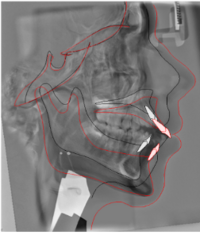

Foto retinerade hörntänder

Patient som har sina primära hörntänder kvar eftersom de permanenta hörntänderna ligger kvar uppe i käken.

Foto: Maria Ransjö

Röntgenbild som visar permanenta hörntänder som inte erupterat.